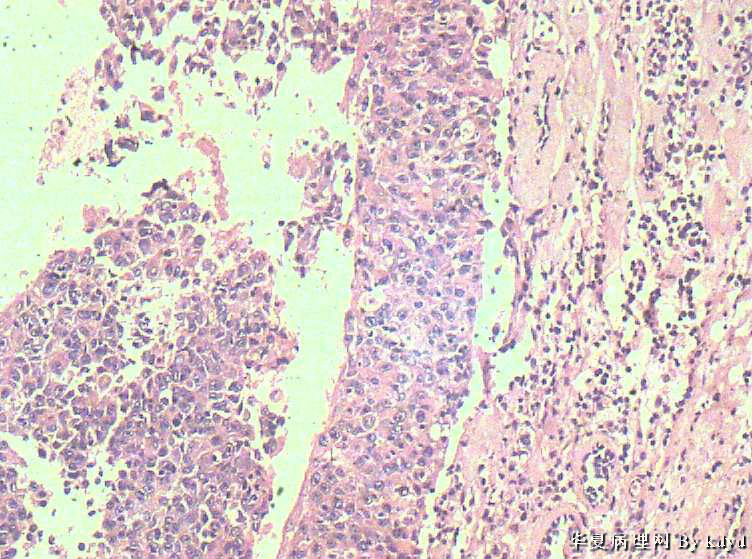

B3997左乳肿瘤--浸润性导管癌?

37岁,女。左侧乳腺肿块发现5个多月,伴隐痛。

手术见:肿块与周围组织分界不清,无明显包膜。

大体:不整形组织大小约3.5*35*2CM,未见明显包膜。质较软,切面浅黄色,一侧见一小囊腔直径约0.8CM囊壁较粗糙。

标签:乳腺浸润性导管癌 原位癌

浸润性乳腺导管癌?

IDC

乳腺浸润性导管癌

囊壁内大量炎细胞浸润,囊壁被覆细胞有明显异型,可见核分裂,考虑癌,不知有无陷阱

浸润性导管癌

应该是个浸润性导管癌

但是,片子质量欠佳

不太敢直接下

诊断乳腺浸润性导管癌确实有些担心,制片质量确实要提高,制作优良的切片,是正确诊断的前提。